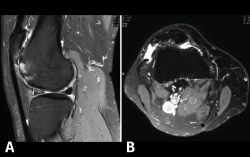

Figura 52. A: corte de secuencia coronal T2 Fat-Sat con infartos óseos en el fémur y la tibia; B: corte de secuencia sagital T1 con infartos óseos en el fémur y la tibia.

4.3. Osteocondritis

Los infartos medulares óseos aparecen en el 0,06% de los pacientes a quienes se les ha realizado una RM del aparato locomotor. Se presentan como lesiones segmentarias, puramente medulares, sin afección cortical, normalmente múltiples y que afectan predominantemente a los huesos largos de las extremidades, sobre todo las inferiores. La RM es esencial en el diagnóstico por imagen, apareciendo como lesiones óseas intramedulares de contornos serpiginosos hipo- o isointensos en secuencias T1 e hiperintensos en T2. Por tanto, la RM es el instrumento crucial en las fases iniciales, ya que permite caracterizar las lesiones y proceder a su diagnóstico temprano(19)(Figura 52).